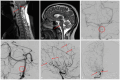

Cerebral vasculitis is a rare but severe manifestation of neurosarcoidosis (NS) that has received little attention. The aim of the present study was to characterize clinical and diagnostic features as well as potential treatment strategies of cerebral vasculitis related to NS. We assessed 29 patients with cerebral vasculitis related to NS (15 female, mean age at time of diagnosis 45 years, SD = 11.85) among these were four new cases from our hospital records and 25 previously published cases from a systematic literature review. The demographic, clinical, and diagnostic features of those 29 patients with cerebral vasculitis related to NS were compared with a group of 73 NS patients without vasculitic involvement (37 female, mean age at time of diagnosis 47 years, SD = 14.79). Neurologic deficits and MRI abnormalities were significantly more frequent in cerebral vasculitis related to NS than in NS without vasculitic involvement. Patients with cerebral vasculitis related to NS significantly more often presented with headache, motor symptoms, and cognitive and/or behavioral changes. Non-neurologic manifestations of sarcoidosis did not significantly differ in character or frequency between both groups. Glucocorticoids in combination with methotrexate, cyclophosphamide, or infliximab were the most frequently used treatment strategies in cerebral vasculitis related to NS. Within the complex diagnostic work-up that is required in cerebral vasculitis related to NS sufficient angiographic imaging as digital subtraction angiography or MRI vessel wall imaging and tissue biopsy are of particular significance as they can detect vascular changes caused by inflammatory processes.